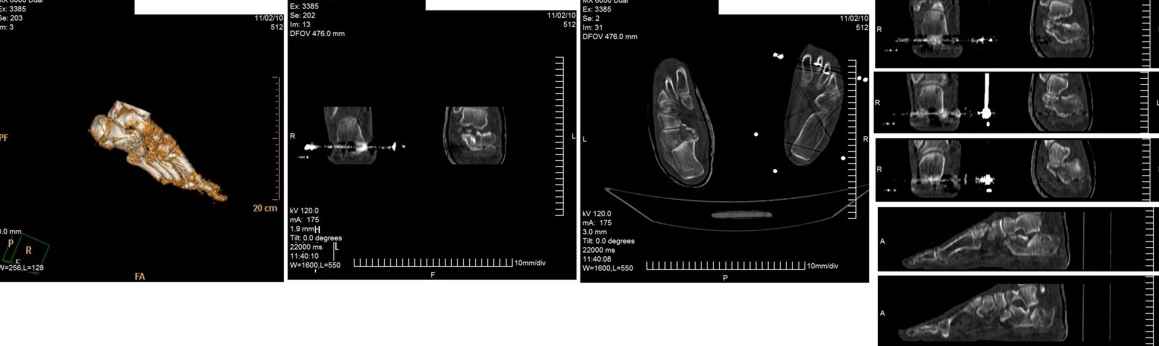

Опираясь на опыт пятидесяти выполненных операций при переломах пяточной кости, мы бы поступили следующим образом.

Безусловно, если есть возможность выполнить КТ подтаранного сустава и пяточной кости до оперативного вмешательства, его необходимо выполнять. Это облегчит планирование оперативного вмешательства. Но для того чтобы решить, что больному в данном конкретном случае необходима открытая репозиция перелома и остеосинтез, достаточно рентгенограммы. Форма пяточной кости сохранена и после репозиции просевшей суставной поверхности пяточной кости угол Белера будет восстановлен. Другим способом, кроме открытой репозиции, поднять просевшую суставную поверхность пяточной кости не представляется возможным. L-образный разрез с латеральной стороны, огибающий латеральную лодыжку. Разрез не должен иметь острых углов (всегда присутствует угроза некроза кожи), сразу доходить да пяточной кости. Отсепаровывать лоскут необходимо сразу от латерального кортикального слоя пяточной кости. В данном случае не следует располагать разрез слишком низко к подошвенной поверхности стопы, так как потребуется только вскрыть подтаранный сустав. Отводятся кверху сухожилия малоберцовых мышц, приподнимается и отводится в сторону сломанная кортикальная пластинка латеральной поверхности тела пяточной кости, поднимается элеватором кверху просевшая суставная поверхность пяточной кости и плотно прижимается к суставной поверхности таранной кости. Проводится две спицы, диаметром 2 мм через пяточный бугор, репонированную суставную поверхность пяточной кости в таранную кость. Скорее всего, потребуется костная пластика образовавшегося дефекта в пяточной кости спонгиозным костным трансплантатом из крыла подвздошной кости. Поскольку у больного повреждены все конечности и вертикализировать его в ближайшие три месяца вряд ли представляется возможным, фиксация двумя спицами будет достаточной. Выполняется интраоперационная рентгенография в двух проекциях. Латеральная кортикальная пластинка тела пяточной кости укладывается на место. Дополнительной её фиксации, как правило, не требуется. Обычно, мы заканчиваем операцию дренированием раны дренажной системой низкого вакуума.

Извините за столь подробное описание. Если необходимо, в понедельник вышлю рентгенограммы похожих случаев.

С уважением, VlaD.

С моей точки зрения, в данном конкретном случае перелом пяточной кости весьма схож с импрессионными переломами латерального мыщелка большеберцовой кости, когда проваливается только часть суставной поверхности большеберцовой кости, а форма и размеры мыщелка остаются прежними. Поэтому после репозиции нет необходимости в применении массивных имплантантов, большую пользу принесёт костная пластика. В представленном случае длина пяточной кости сохранена, нет типичной варусной деформации отломков на КТ, а спицы нужны лишь для фиксации фрагмента пяточной кости с суставной поверхностью в репонированном положении на суставной поверхности таранной кости. При сращении перелома в таком положении функция подтаранного сустава будет обеспечена, а при сохранённых форме и размерах пяточной кости следует ожидать безболезненной нагрузки.

VlaD.